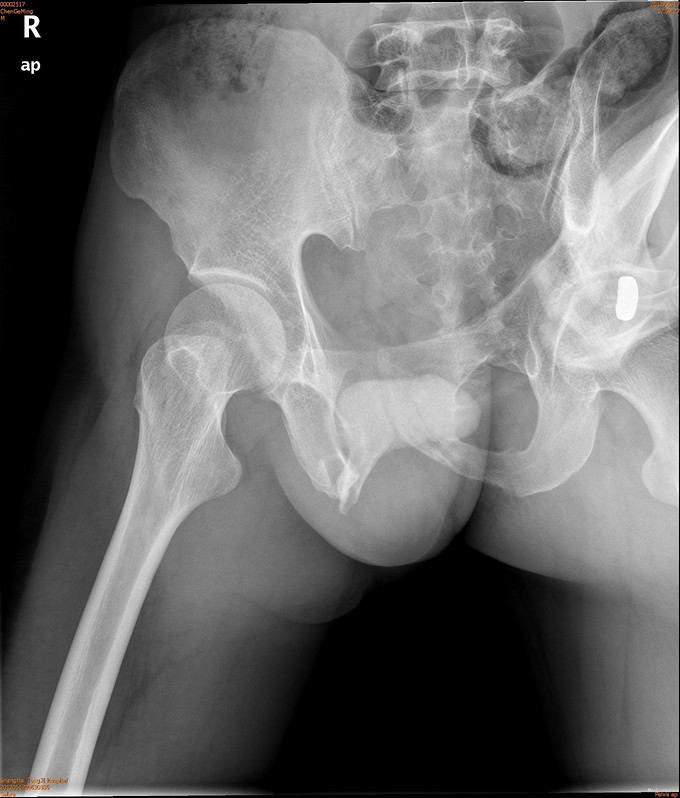

患者男,41岁,因车祸致双侧髂腰部、中下腹部及会阴部疼痛,伴尿道出血1小时。患者于1小时前不慎被汽车撞伤,当即感到双侧髂腰部、中下腹部及会阴部剧痛,尿道口有鲜血渗出,有昏迷,后自行苏醒,120送入我院急诊,CT示两侧骶髂关节前缘骨折,双侧耻骨上下支骨折,周围血肿形成。急诊导尿失败,遂入院治疗。

诊断为耻骨上下支骨折,兄弟科室会诊治疗结束后,患者病情稳定,行切开复位内固定术。